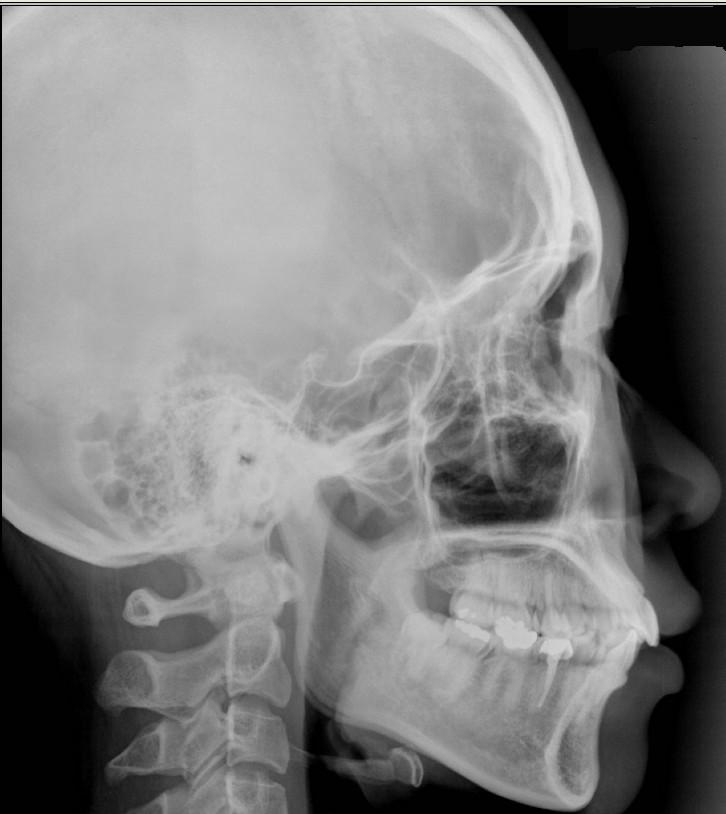

치아가 고르고 상악은 보통 사이즈, 하악은 오히려 작아서 더 돌출처럼 보이며

(상악 양쪽에 덧니가 있으나 보이지 않음)

단순 교정으로는 효과를 볼 수 없으며 오히려 푹 꺼진 느낌이 날 수 있고

수술을 해도 최대 2mm 정도 들어갈 지 모르겠다고 하시더라구요ㅠ

제 사진을 첨부해봅니다ㅠ